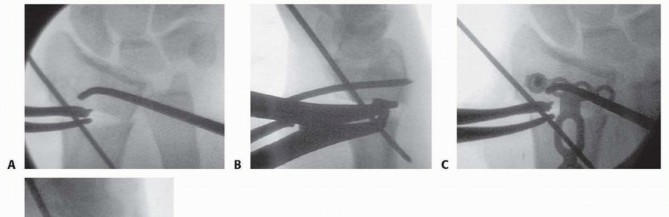

** Intra-articular Distal Radius Osteotomy **Intra-articular osteotomy should be attempted only when there is a simple fracture line that can be clearly identified by direct visualization as well as under image intensification ( TECH FIG 6A-C). Incompletely healed fractures (fewer than 3 to 4 months since injury) are ideal. Depending on the locations of the malunited articular fragments, perform either a dorsal or a volar exposure in the manner detailed earlier. When a dorsal exposure is used, a transverse capsulotomy allows access to the joint and monitoring of the articular osteotomy and realignment. In the case of a volar exposure, the capsule is not incised, but articular exposure may be possible through the osteotomy site. The osteotomy should recreate the original fracture line. This is monitored directly and under image intensification. Reduction is accomplished by soft tissue release and direct fragment manipulation. For many malunions, it is necessary to remove bone or callus from the fracture site to realign the fracture fragment. Callus or bone is removed until the fracture fragment fits properly ( TECH FIG 6D). Provisional Kirschner wires are used to hold the reduction ( TECH FIG 6E,F). The implants are then applied. Dorsally, a single T- or Pi-shaped plate or two 2.0- or 2.4-mm plates (one applied dorsally, ulnar to the tubercle of Lister, and the other applied radially between the first and second dorsal compartments) can be used ( TECH FIG 6G,H). Volarly, a T-shaped plate is usually used. After final plate fixation, provisional fixation is removed. This entire process is monitored using image intensification to confirm appropriate osteotomy site, correction of alignment, and implant placement. Deflate the tourniquet, close the wound, and apply the splint in the manner detailed earlier. 150

### TECH FIG 6 • A-C. PA and lateral radiographs and CT of an intra-articular dorsally angulated malunion. D. A Freer elevator is used under fluoroscopy to reposition the articular fragment. E,F. Intraoperative fluoroscopic views showing provisional correction and fixation. G,H. Final plate and screw fixation. (Copyright Diego Fernandez, MD, PhD.)